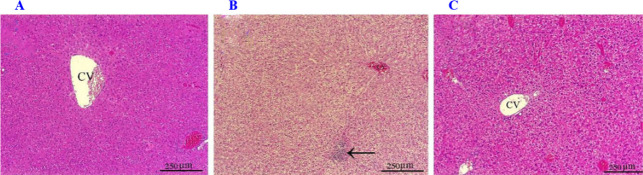

Findings/results: The results of the study showed that the expression levels of the genes Smad3 and miRNA- 141 were significantly reduced in the resveratrol-treated group compared to the NAFLD group, while the expression levels of SIRT1 and TGF-β were significantly increased. In addition, the Western blot results indicated that the levels of the proteins P-AMPK and SIRT1 in the resveratrol-treated group were significantly higher compared to the NAFLD group. Furthermore, a significant reduction in fat accumulation and degeneration was observed in the histopathological findings of the liver in the resveratrol-treated group.